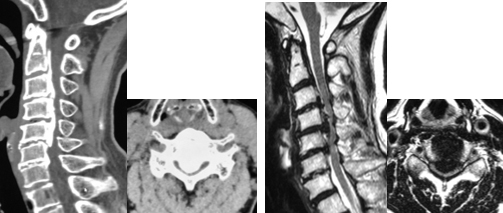

後縦靭帯骨化症 骨化巣摘出・浮上術

後縦靭帯骨化症で骨化巣が大きい場合に、有効な術式となります。後縦靭帯骨化症では、骨化巣が神経の膜と連続していることがあり、剥離は困難なことがあります。摘出が困難な場合には、骨化巣を浮上させて神経症状の改善をはかる方法もあります。

頚椎後方除圧固定術

対象となる疾患:頚椎症性脊髄症、頚椎後縦靭帯骨化症、頚椎椎間板ヘルニア、脊椎腫瘍など

頚椎後方除圧固定術は、頚椎の後方からアプローチして、圧迫因子となっている骨や靭帯を削除したり、金属製のスクリューなどで頚椎を固定する手術法です。頚椎に不安定性があったり、後弯と言って骨の並びが後ろに弯曲している場合などで有効な手術法となります。通常、手術翌日より座位や歩行訓練を行います。術後は、頚部を固定する装具を約1−3カ月装着します。

手術前のCTおよびMRIでは、椎体の後ろにある骨化した後縦靭帯が脊柱管内に大きく占拠し、脊髄を強く圧迫しています。

前方から椎体切除および骨化巣の浮上術を行い、代わりに金属製のケージを設置しました。非常に高度な狭窄であったため、後方からも除圧を追加し、頚椎のカーブを維持するためにスクリューとロッドによる固定を行いました。術後、神経症状は著明に改善しています。